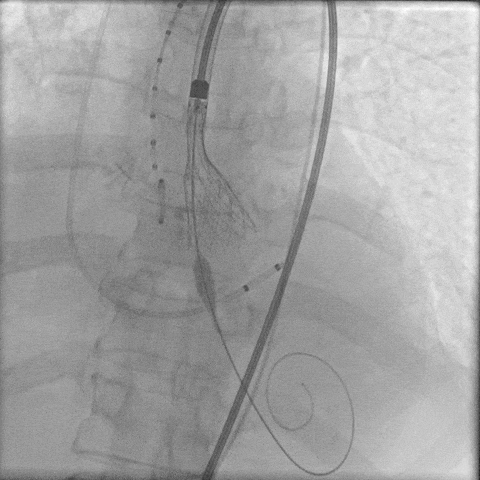

主动脉根部造影,主动脉狭窄伴有明显反流,采用18mm球囊预扩,轻微腰征,造影无漏。

主动脉根部造影

球囊预扩

TaurusElite 输送器轻松过弓、跨瓣,LAO 11° CRA 15°投照角度下,第一次定位。

TaurusElite轻松过弓

第一次定位

第一次释放后,造影评估深度偏深,随即完全回收。

第一次释放

第一次回收